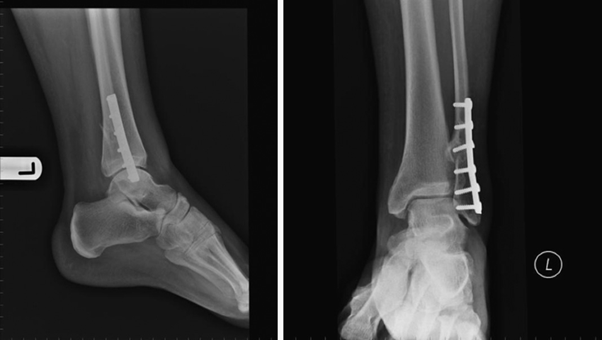

Inadequate bony healing is seen 9-week post op on x-ray

- Malunion occurs when fractured bones heal improperly, causing misalignment. Non-union refers to fractures that fail to heal altogether.

- Both conditions lead to altered biomechanics, abnormal stress on the ankle joint, and persistent pain.

- Symptoms include deformity, instability, swelling, and pain exacerbated by weight-bearing or physical activity.

- Common in cases of neglected fractures or inadequate surgical fixation.